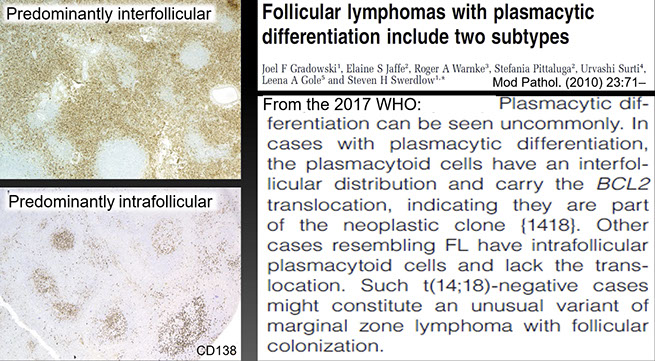

1 - 8